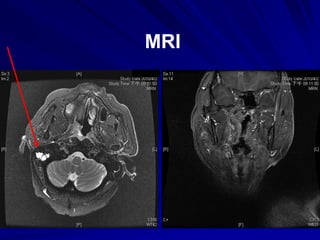

Normal Nasopharynx

NPC Clinical

Presentations

MRI